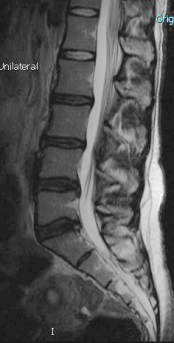

MRI images can be baffling! In this study, 11.2% of patients who complain of pain on one side actually have MRIs showing herniations on the other side! The researchers suggest “further investigation to avoid missing the diagnosis and treatment failure” for back pain(1) Of course! Your St Peters chiropractor knows to rely on clinical examination findings - how your body is responding - and correlate with MRI images. Your St Peters chiropractor is the back pain specialist to see! The body tells so much more than an image!